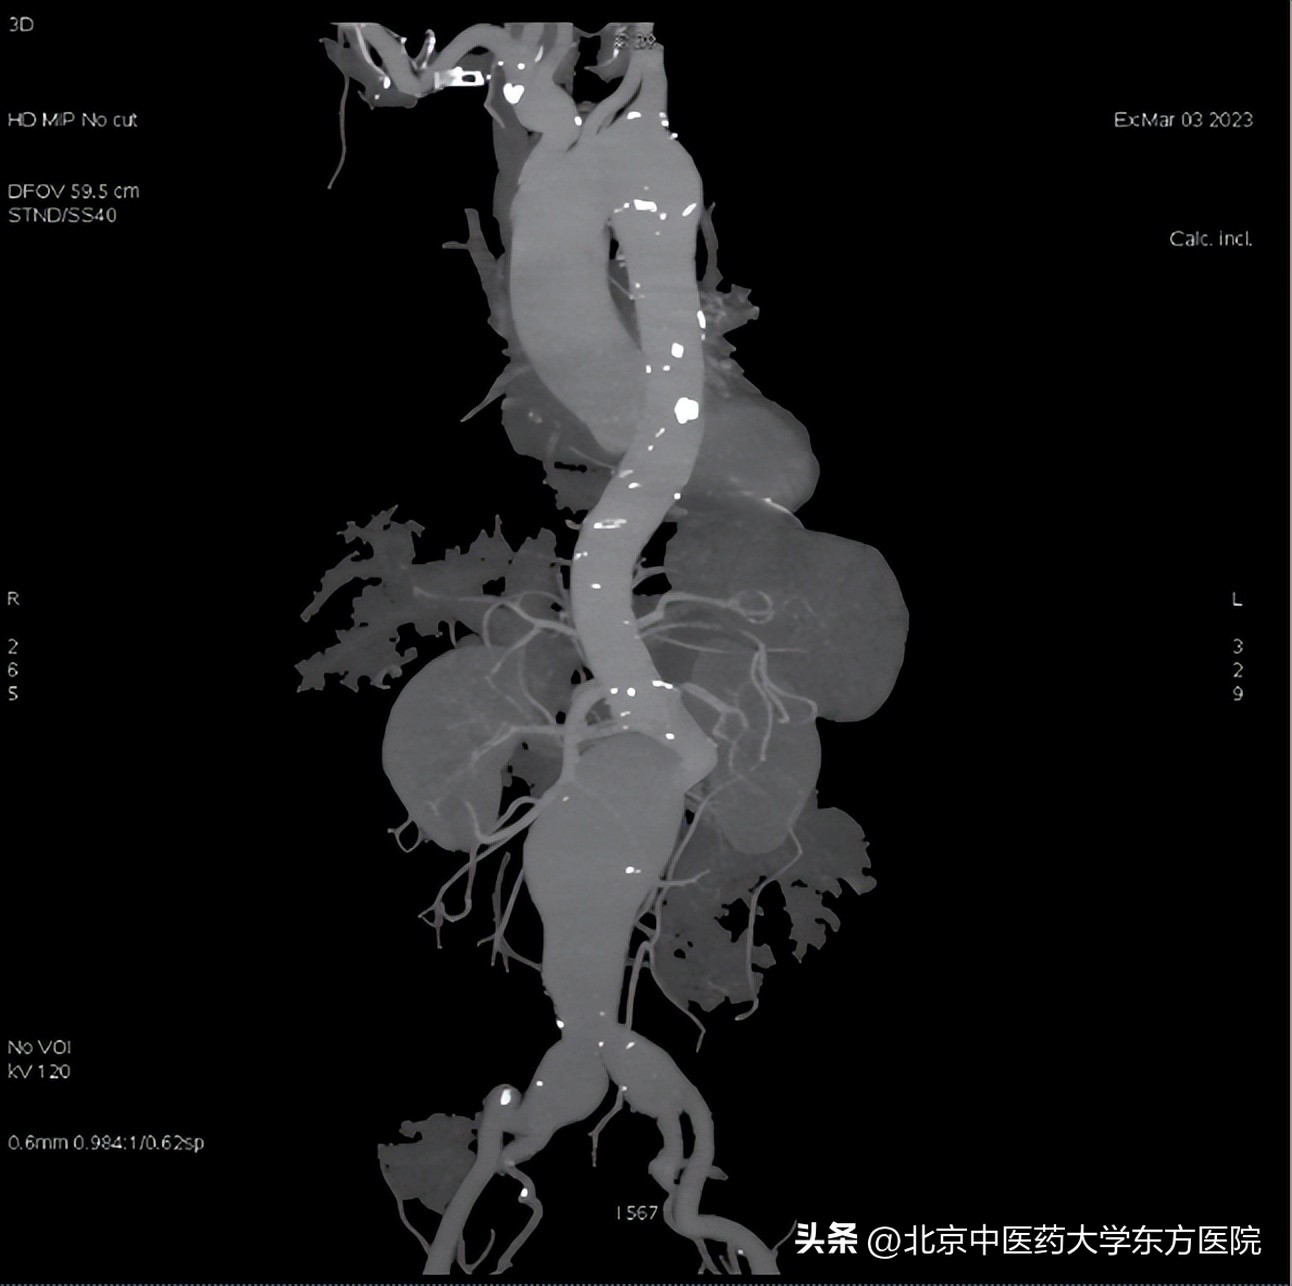

本次完成的双侧IBD患者为男性,68岁,以“发现腹主动脉瘤半个月”入院。入院时完善CT检查,患者瘤体直径73.8mm,属于巨大的重度扭曲先兆破裂的腹主动脉瘤,随时有破裂的风险,由于病变累及双侧髂动脉,手术难度巨大。

(术前)